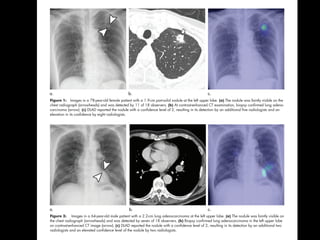

Figure 2. Accuracy of Detecting Atrial Fibrillation in the Cardioversion Cohort

A, Receiver operating characteristic

curve among 51 individuals

undergoing in-hospital cardioversion.

The curve demonstrates a C statistic

of 0.97 (95% CI, 0.94-1.00), and the

point on the curve indicates a

sensitivity of 98.0% and a specificity

of 90.2%. B, Receiver operating

characteristic curve among 1617

individuals in the ambulatory subset

of the remote cohort. The curve

demonstrates a C statistic of 0.72

(95% CI, 0.64-0.78), and the point on

the curve indicates a sensitivity of

67.7% and a specificity of 67.6%.

Table 3. Performance Characteristics of Deep Neural Network in Validation Cohortsa

Cohort

%

AUCSensitivity Specificity PPV NPV

Cardioversion cohort (sedentary) 98.0 90.2 90.9 97.8 0.97

Subset of remote cohort (ambulatory) 67.7 67.6 7.9 98.1 0.72

Abbreviations: AUC, area under the receiver operating characteristic curve;

NPV, negative predictive value; PPV, positive predictive value.

a

In the cardioversion cohort, the atrial fibrillation reference standard was

12-lead electrocardiography diagnosis; in the remote cohort, the atrial

fibrillation reference standard was limited to self-reported history of persistent

atrial fibrillation.

AUC=0.98 AUC=0.72

• In external validation using standard 12-lead ECG, algorithm

performance achieved a C statistic of 0.97.

• The passive detection of AF from free-living smartwatch data

has substantial clinical implications.

• Importantly, the accuracy of detecting self-reported AF in an

ambulatory setting was more modest (C statistic of 0.72)